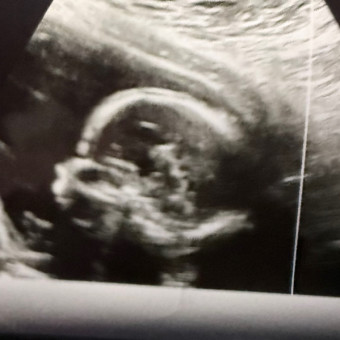

Babylist Registry Photo

Baby Moreno

June 21, 2026